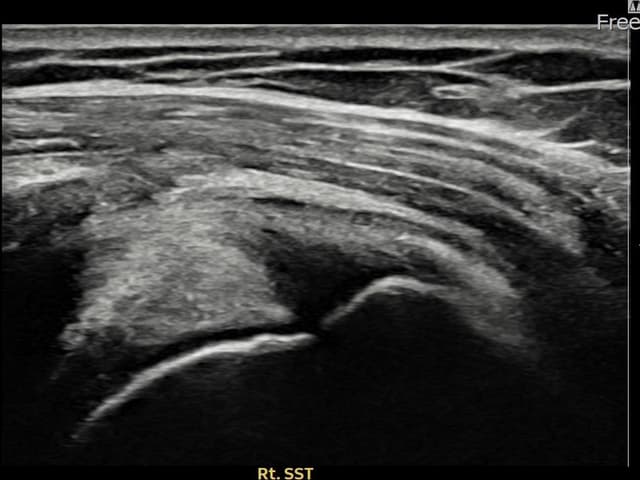

[촬영시기:22.09.19~22.12.09]

[어깨인대 축소봉합술] 우측 어깨 통증이 수개월간 지속되어 내원하셨습니다.